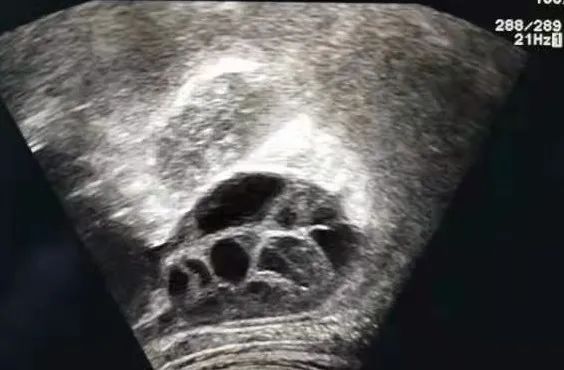

腹部超声下右侧卵巢在肋下缘

腹部超声引导下定位、穿刺